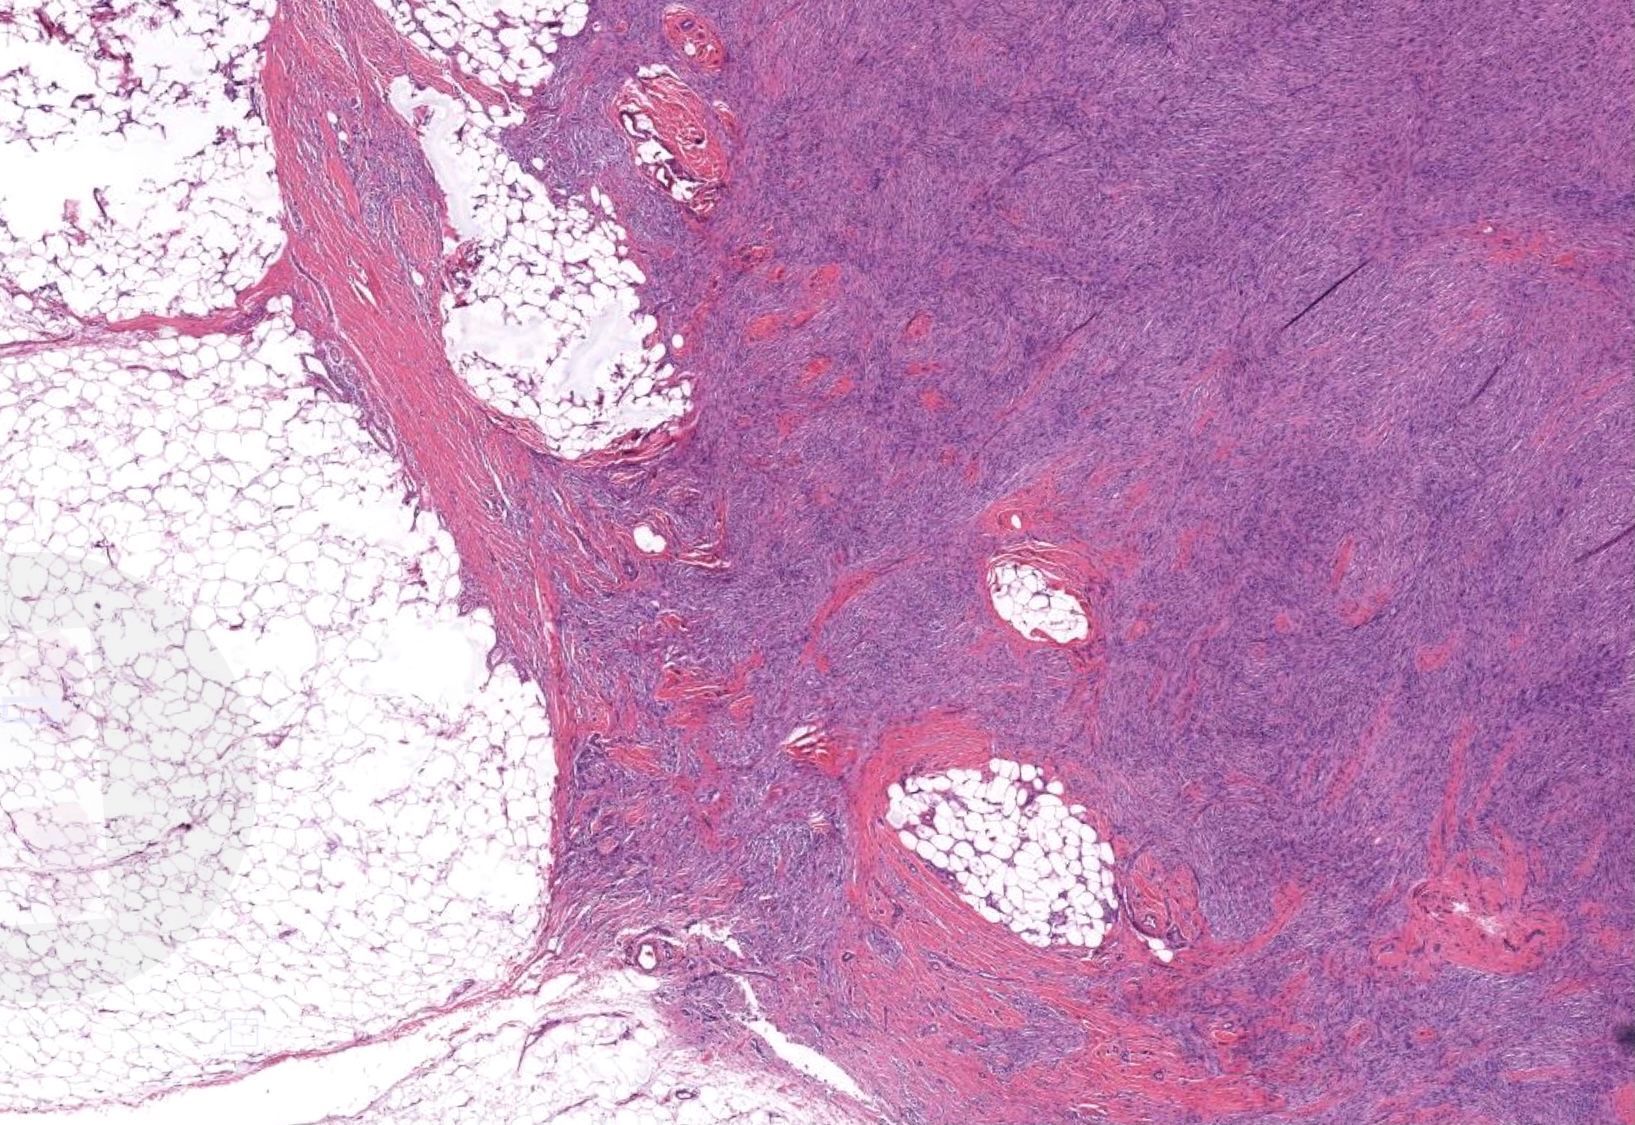

Vulvar skin biopsy. Erythematous pruritic eruption. Your diagnosis?

Only H&E stain needed for this one!